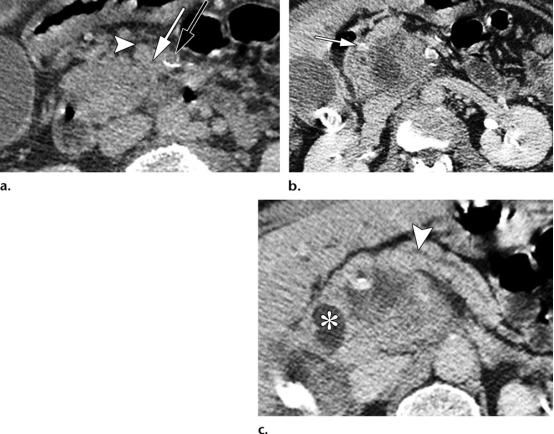

49岁女性,胰腺头部的肿块形成型慢性胰腺炎。

(a图)轴位CT示扩张的主胰管(白色五角形),胰腺实质完整保存,未见明确萎缩。胰管与胰腺实质的比值小于0.5,胰腺实质内可见散在钙化灶(白色短箭头);

(b图)冠状位CT图示,胰头区肿块样病变(白色圆圈),胰管突然变窄,并穿透于实质内(黄色长箭头)。

56岁男性,胰头区的胰腺导管腺癌(PDAC)。

(a图)轴位CT图示肠系膜上静脉(白色短箭头)与肠系膜上动脉(黑色长箭头)大小相仿,伴血管周围的软组织密度包裹(白色长箭头)。肠系膜上静脉的轮廓异常。

(b图)轴位CT图示,胰头区局灶浸润性低密度肿物,侵及胃十二指肠动脉(白色长箭头)。

(c图)轴位CT图示远端胰管的管径正常,胰腺实质也保存完好(白色短箭头),注意观察扩张的胆总管远端(白色*),未见胰腺实质背景的钙化。